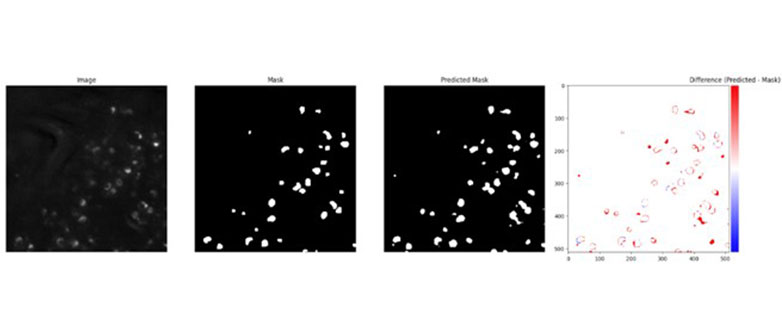

Wir haben verschiedene Modelle aus dieser Studie – U-Net, BTUNet, YOLOv8x-seg, YOLOv8x+SAM und HoverNet – auf einen von IMAI bereitgestellten Datensatz angewendet. Ziel des Projekts war es, verschiedene Modelle hinsichtlich Genauigkeit und Effizienz bei der Segmentierung von Krebszellen zu vergleichen und so die optimale Balance zu finden.

Unsere Forschung liefert wertvolle Erkenntnisse, die die Krebsfrüherkennung und -diagnostik erheblich verbessern können. Unter den von uns getesteten Modellen zeigte HoverNet die höchste Segmentierungsgenauigkeit und ist damit die verlässlichste Wahl für präzise Krebsdetektion. BTUNet überzeugte insbesondere bei eingeschränkt beschrifteten Datensätzen und bewies die Wirksamkeit von selbstüberwachtem Lernen durch stabile Vorhersagen. YOLOv8x-seg stach durch seine Geschwindigkeit hervor und ist daher ein vielversprechender Kandidat für Echtzeitanwendungen – allerdings mit einem kleinen Kompromiss bei der Genauigkeit.